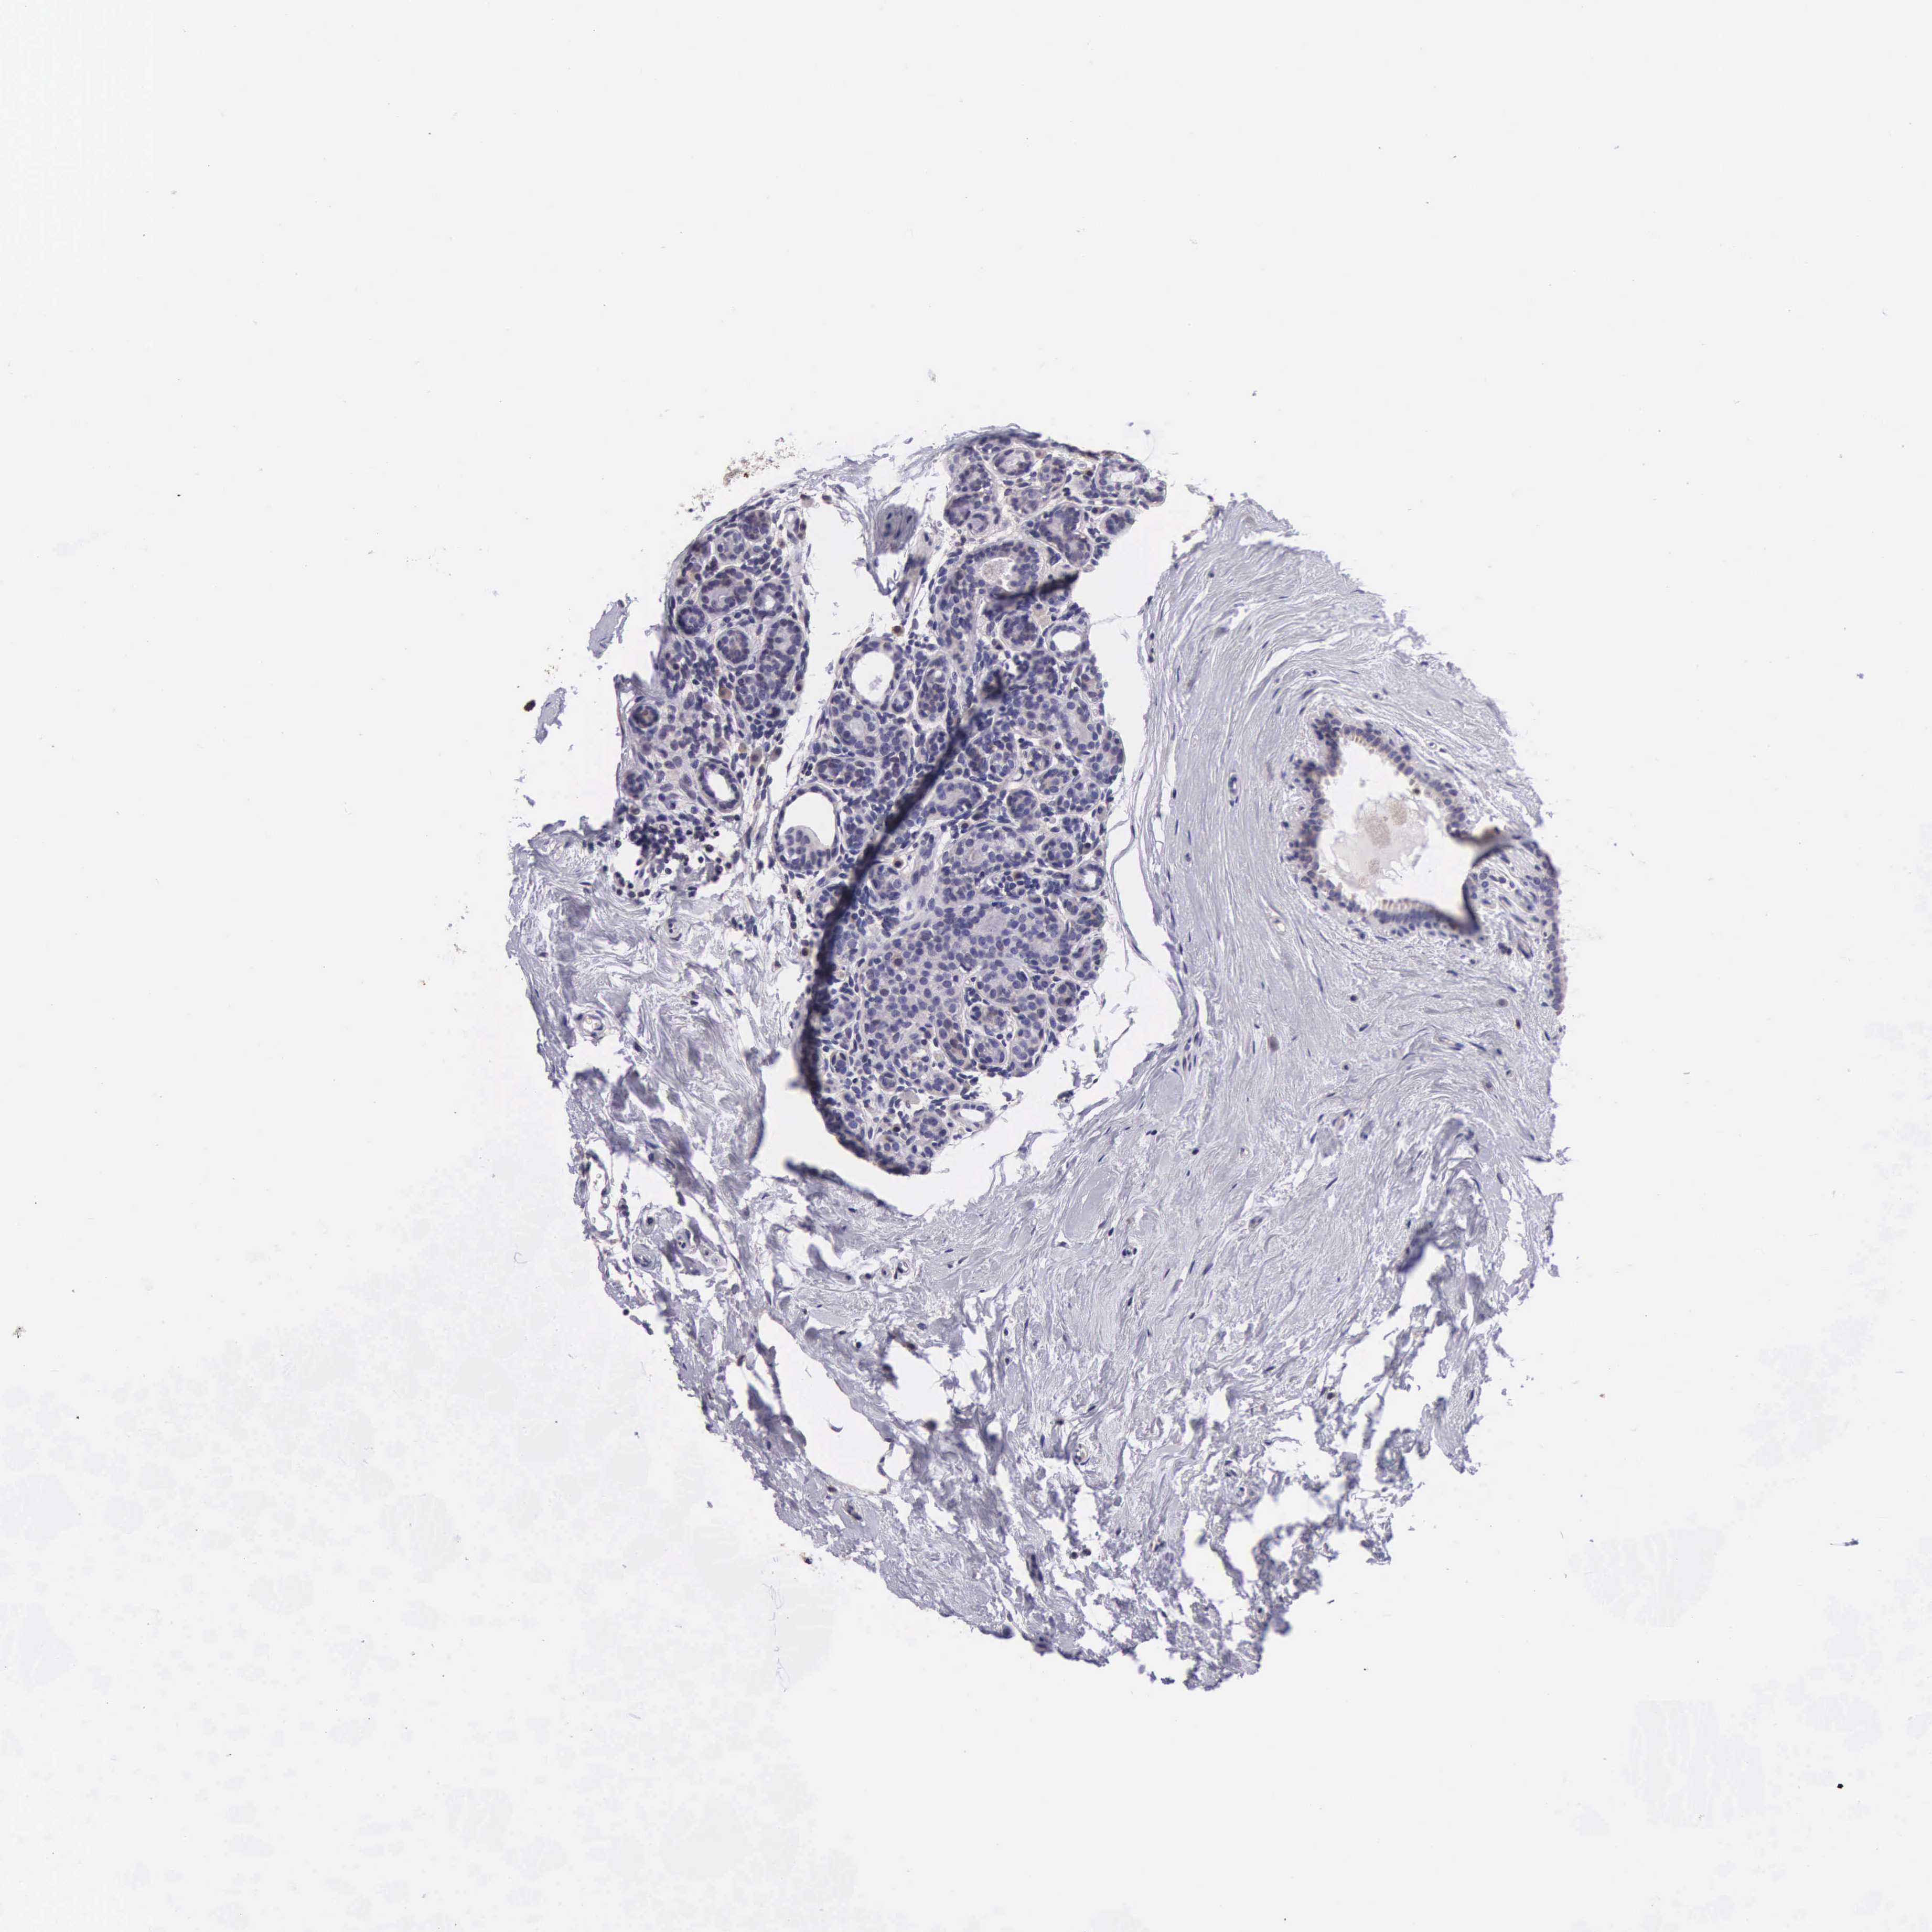

Breast cancer

Human cancer